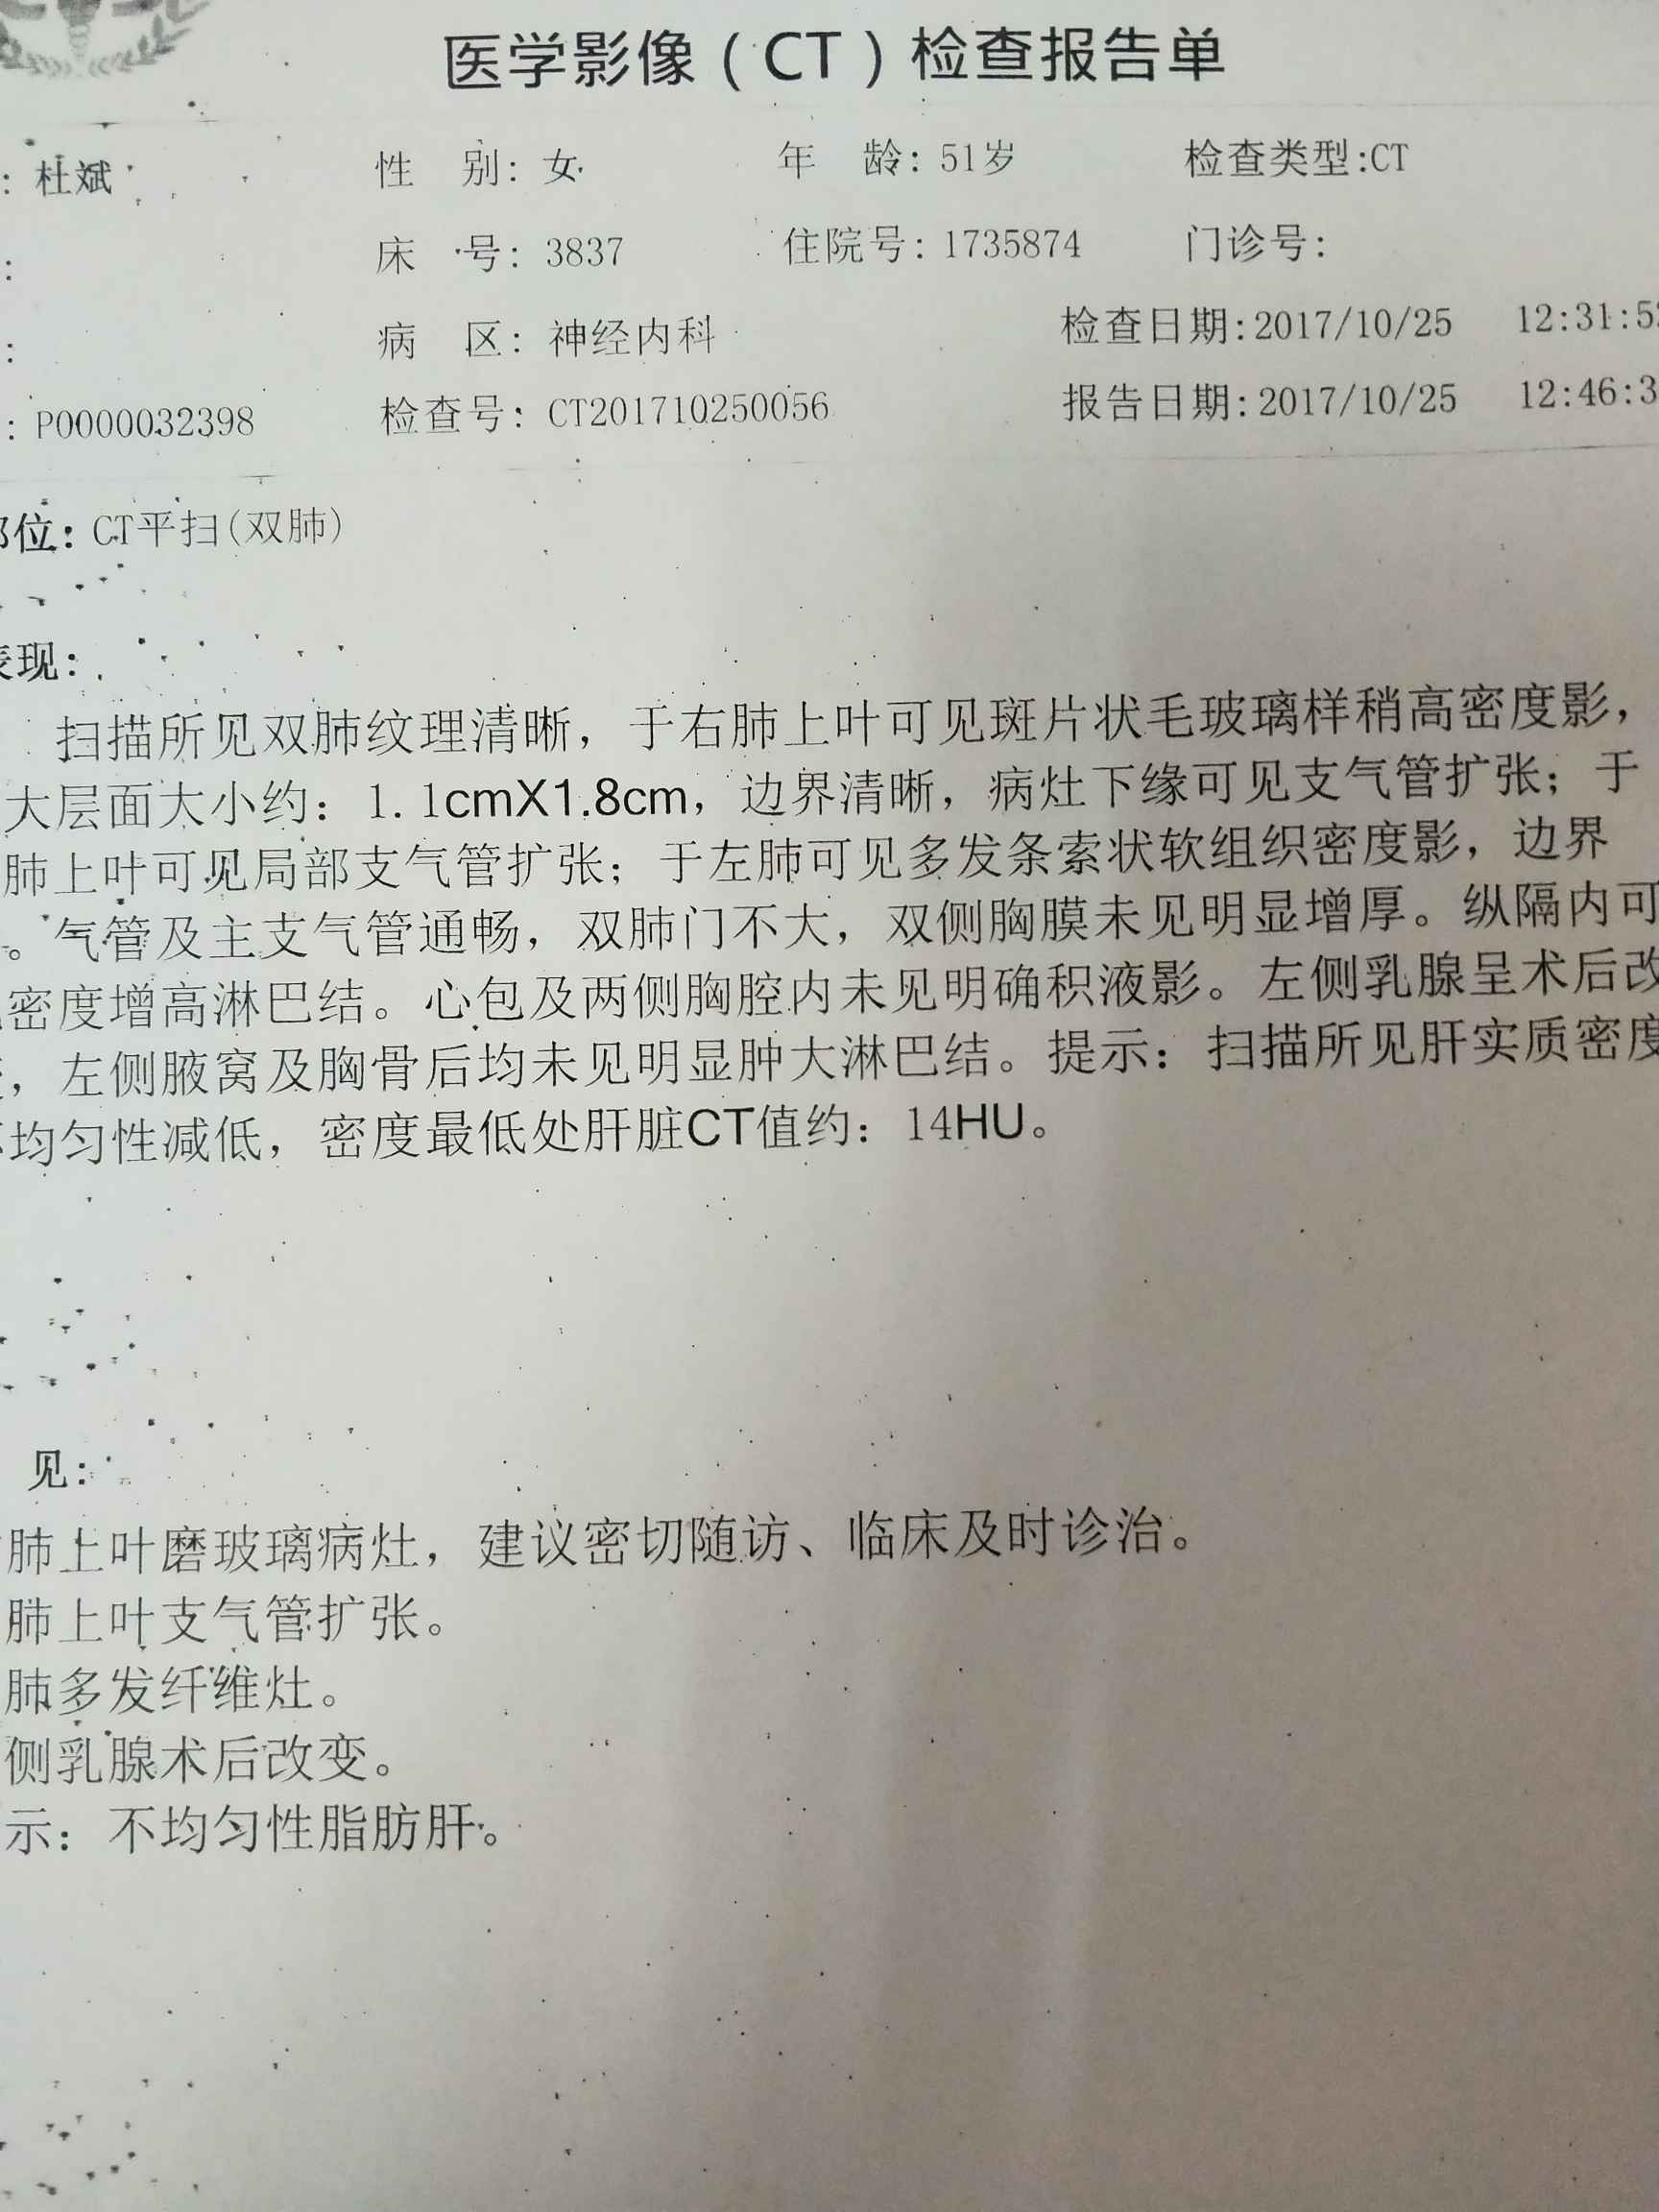

陈波医生病理预测是原位腺癌可能性大,病理出来跟帖回报一下给我看看

报告

陈波医生看到了,可以手术,可以胸腔镜手术,而且属于恶性度比较低的,又是比较早期的

陈波医生不幸遭遇两次肿瘤,幸运的是每次都是早期发现

陈波医生把左右两边的一起拍一个镜头里,应该还是局限在右上肺的原位癌,但还是想看全肺把其他地方排除一下

陈波医生有时间把CT报告发我看看,你是哪个省的,你这个要找手术做得好的,肺癌治疗这个概念太广了